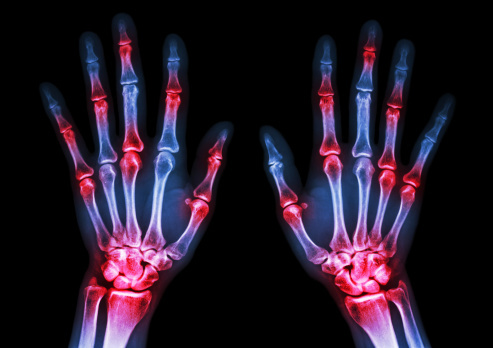

5我的(不那么)小秘密。当所有的方法都失败了,我有一个非常糟糕的一天应对我的双重诊断银屑病和银屑病关节炎,我研究银屑病的照片,真正严重的那些。我的牛皮癣得到了很好的控制。我主要受我的银屑病关节炎的困扰。对我来说,看着红色、发炎斑块的照片提醒我,其他人的情况比我严重得多,这对我有帮助正确看待事物,甚至让我高兴了一点。虽然不好,但这是事实。